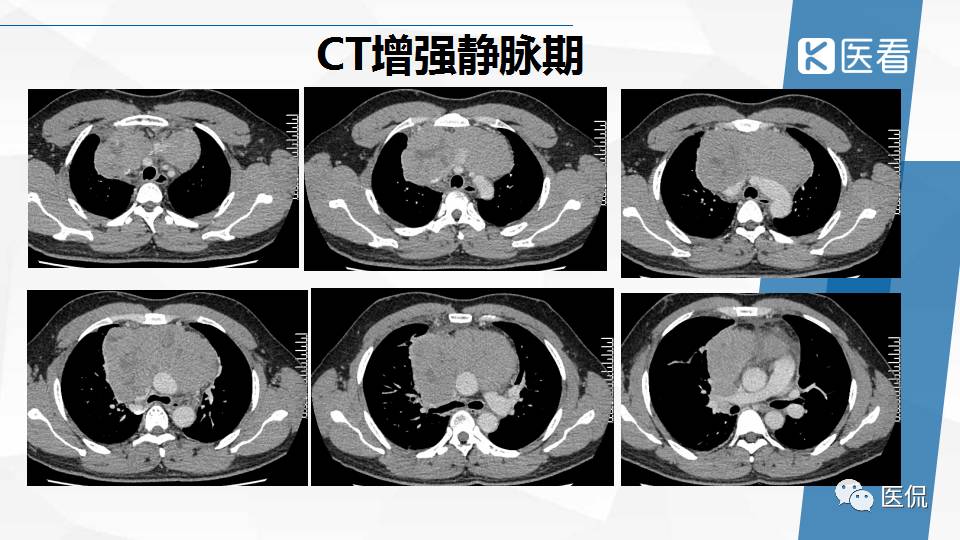

纵隔精原细胞瘤案例 (精原细胞瘤影像表现与鉴别诊断)

精原细胞瘤ct影像,精原细胞瘤影像特征